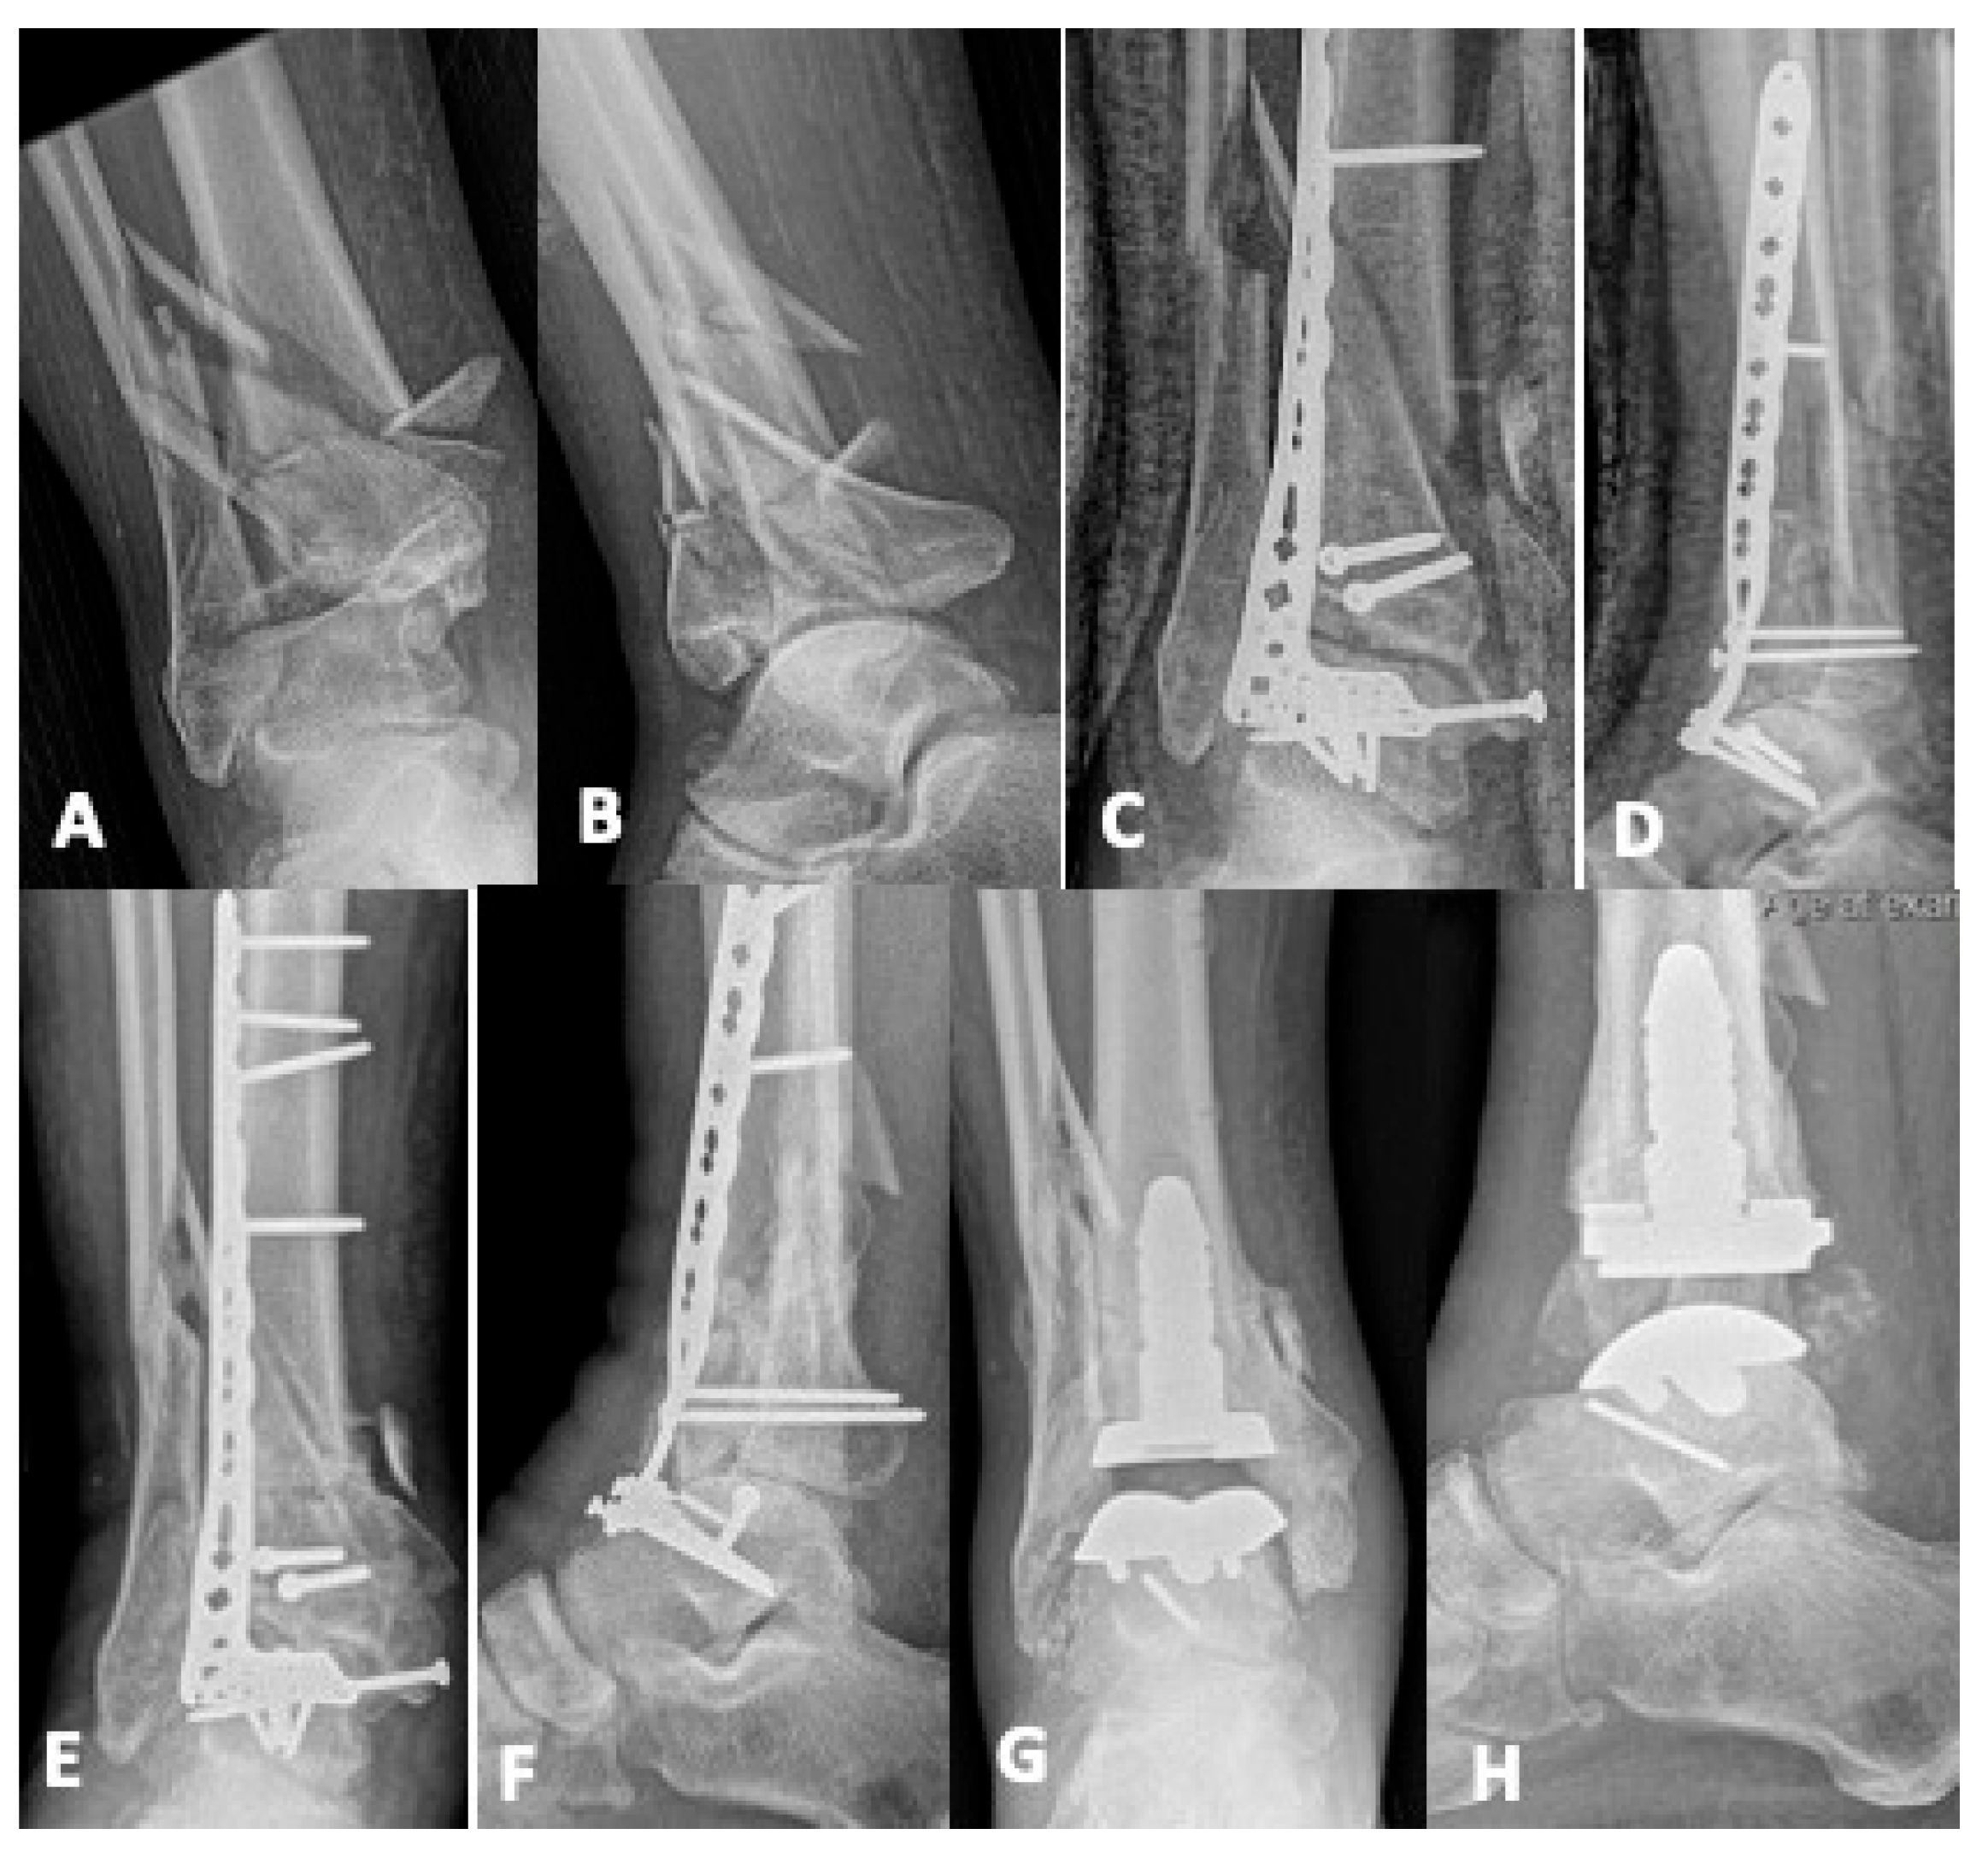

5.2. Joint-Sacrificing Reconstruction

5.2.1. Total Ankle Arthroplasty

5.2.2. Tibiotalar Arthrodesis